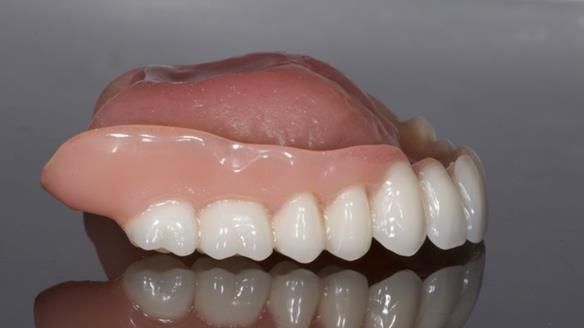

In this edition, I present the complete denture treatment for Kate, a 69-year-old American woman living in Garstang, UK. Kate had been edentulous for many years and required a set of complete dentures that closely mimicked her natural teeth. The new upper and lower dentures provided excellent retention and stability, with significant suction in the upper denture. Below, I detail the step-by-step process of her treatment, as well as my workflow for implant-supported overdentures for patients who may require them.

The treatment was a resounding success, meeting all of Kate’s expectations. While I was confident I could achieve a natural appearance, the challenges of gagging, denture stability, and eating were less predictable and uncertain. I discussed these concerns thoroughly at the outset, and Kate decided to proceed despite the high cost. She expressed that there was no pressure to move forward with the treatment, and she’s been delighted with the life-changing results.